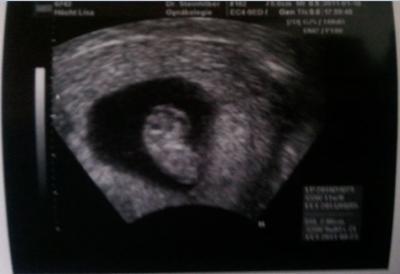

bin wieder zurück von meinem FA Termin... diesmal war er supernett hat sich richtig Zeit für mich genommen... beim Ultraschall hab ich sofort gesehen dass mein Böhnchen riesig geworden ist... es ist jetzt genau 20,06 mm groß... es hat sich sogar umgedreht und mit dem Köpfchen genickt... ich glaub ich bin verliebt... das große runde etwas ist auch 2 cm groß und die Nabelschnur geht da rein der Arzt weiß immer noch nicht was das ist, es ist kein Dottersack aber auch nicht die Plazenta denn das Ding ist nicht durchblutet... naja egal meinem Böhnchen geht´s jedenfalls prima und mir auch ich hab 100 gr abgenommen ist das nicht der Wahnsinn.... ach ja ich bin jetzt in der 9. SSW bei 8+4 der ET ist wahrscheinlich der 26.08. die Schmierblutung am 27.11. war demnach eine Ovulationsblutung und das Krümelchen hat sich trotz Kondom eingeschlichen weil wir erst am 11.12. ohne Verhütung miteinander geschlafen haben... wollte wohl unbedingt bei uns wohnen... lange rede kurzer Sinn ich bin einfach nur happy und könnte die Welt umarmen... jetzt muss ich bloß noch meiner Schwester beibringen dass des Böhnchen an ihrem Geburtstag ET hat... ach und ein Bildle hab ich auch noch für euch... darf ich vorstellen BÖHNCHEN

Bild zu Heute ist ein guter Tag... - Forum für Juni - Mamis